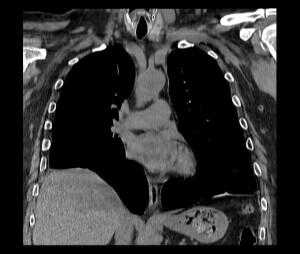

КТ. Наиболее информативным методом исследования является компьютерная томография, дающая полную информацию о степени релаксации и характере изменений органов грудной и брюшной полостей. Во всех случаях релаксации, даже при небольшой ее выраженности, наблюдается ателектаз и воспалительные изменения базальных сегментов легкого. С внедрением компьютерной томографии практически отпала надобность в остальных традиционных методах дифференциальной диагностики.

Релаксация правого купола диафрагмы на КТ

КТ органов грудной клетки/брюшной полости. Травматический дефект в передних отделах диафрагмы справа с эвентрацией кишечника, сальника, кровеносных сосудов в грудную полость